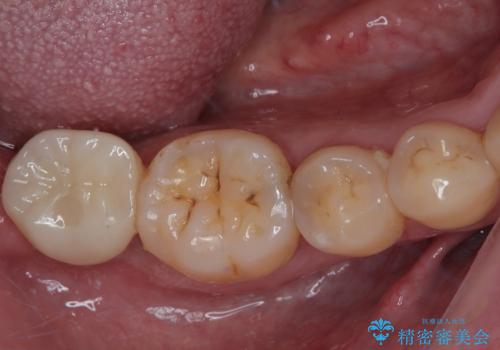

[ 歯槽堤保存術 ] [ 奥歯の破折 ] ソケットプリザベーションを併用したインプラント治療